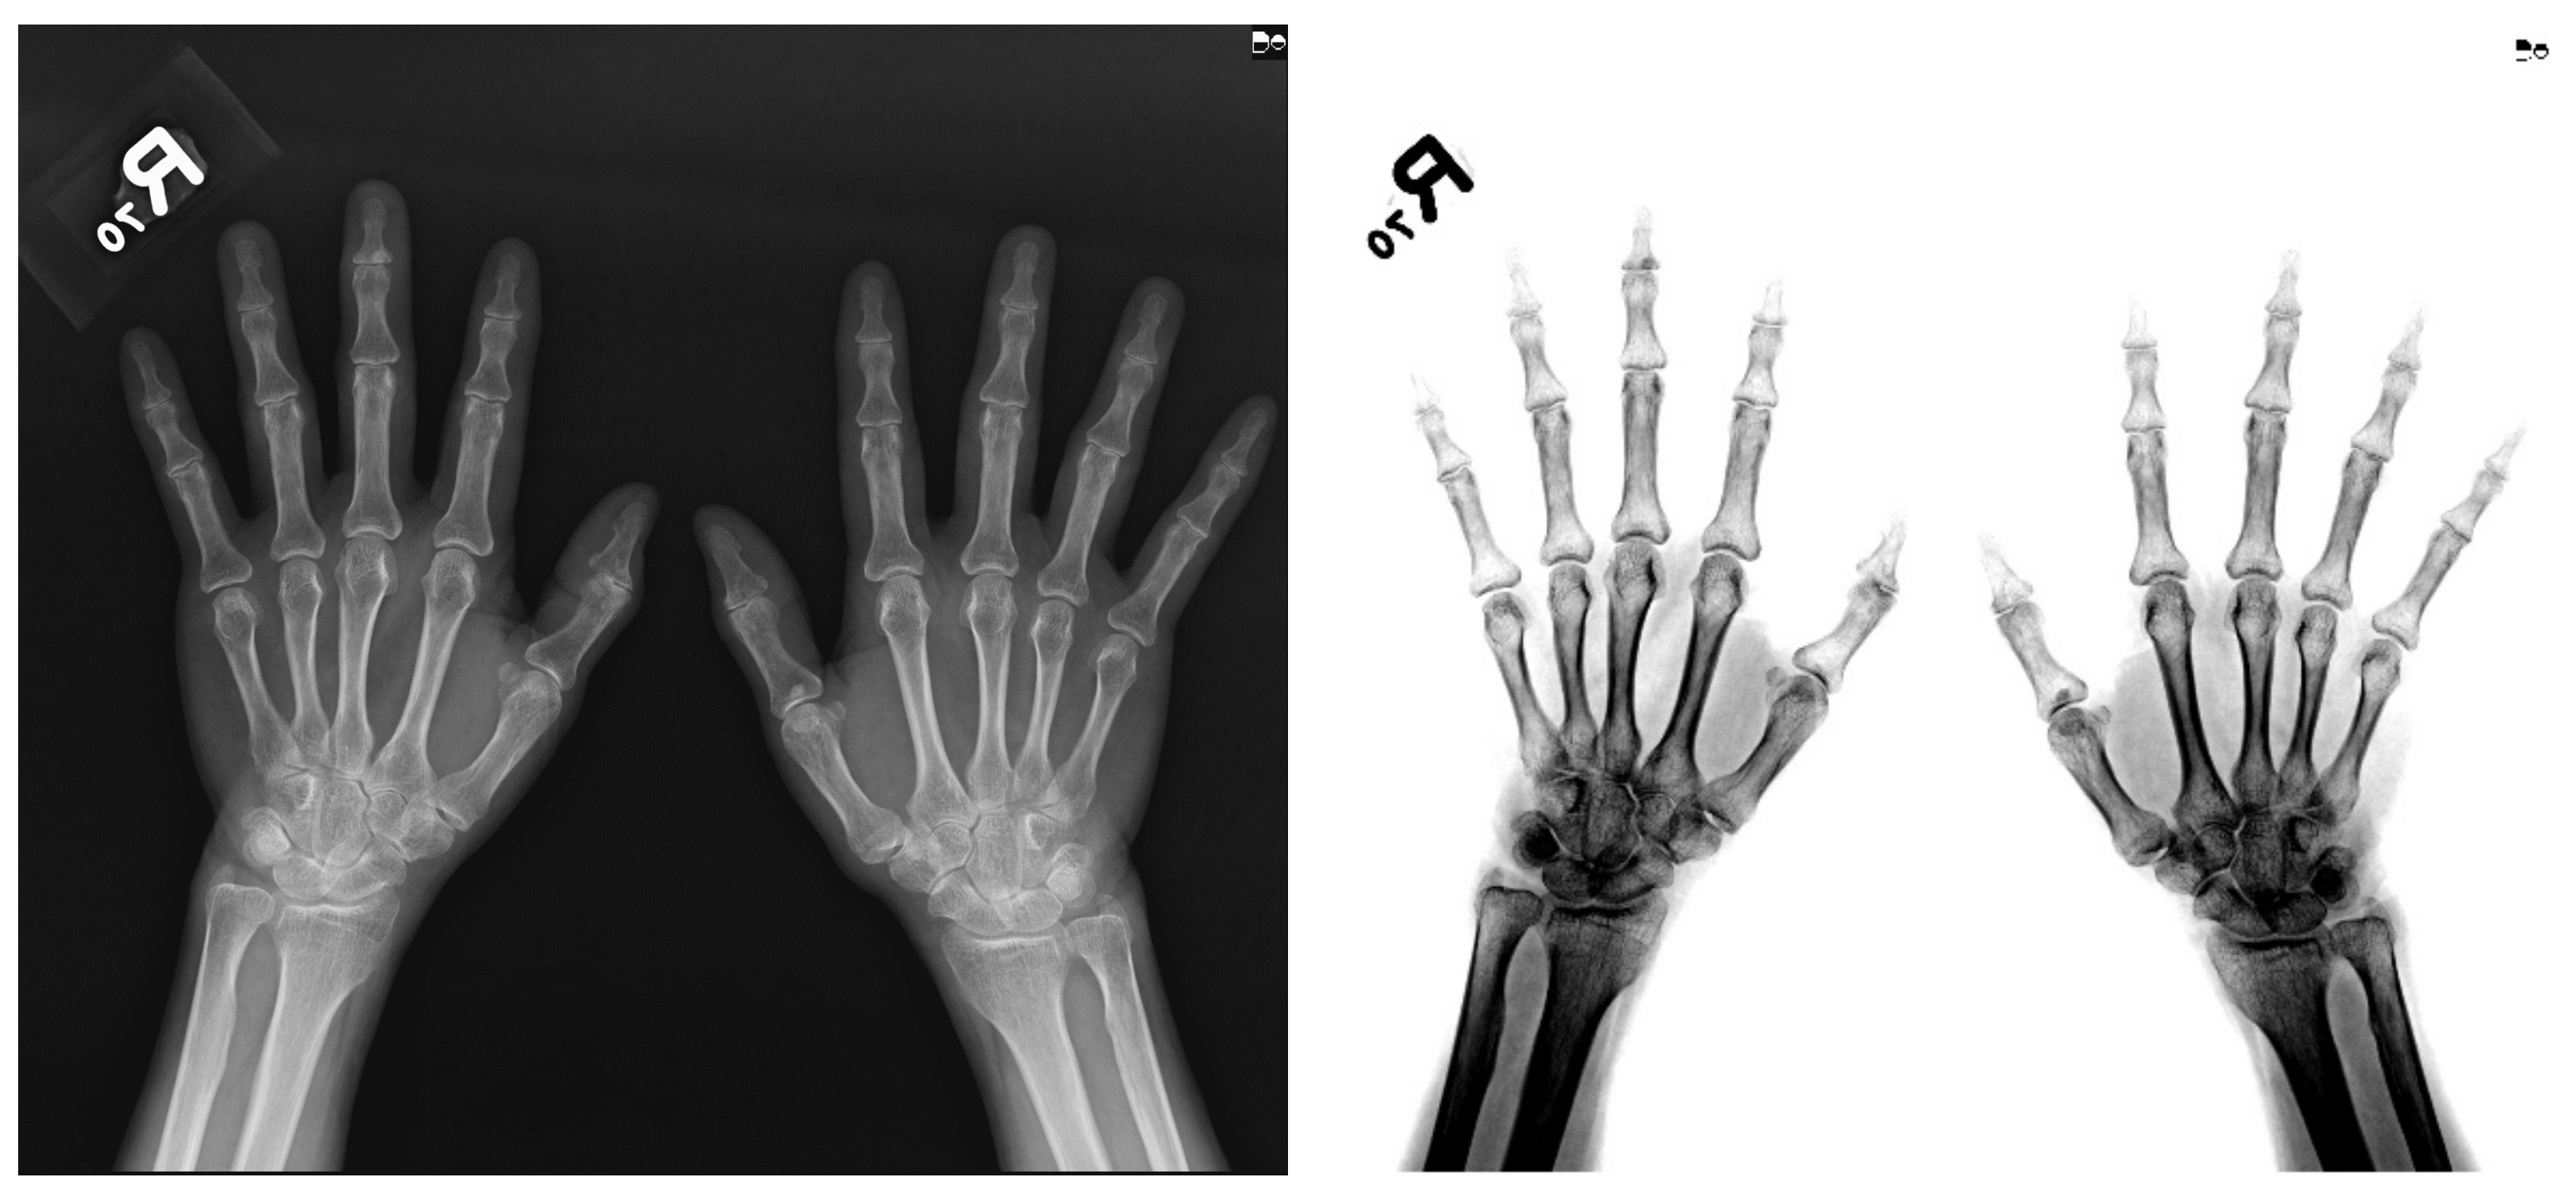

Deep Learning-Based Computer-Aided Diagnosis of Rheumatoid Arthritis with Hand X-ray Images Conforming to Modified Total Sharp/van der Heijde Score

2.1. Image Collection and Deidentification Process

2.2. Definition of ROI